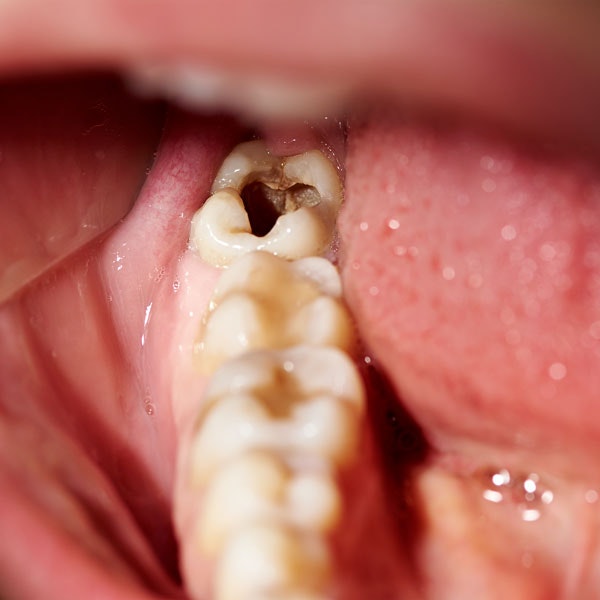

Receive a Surgical Extraction

The dentist may need to create an incision in the gums and remove bone tissue to access the impacted tooth for complex oral problems. In some cases, the tooth will need to be removed in pieces. Depending on the severity, you may need stitches. Again, gauze will be applied to help stop the bleeding.